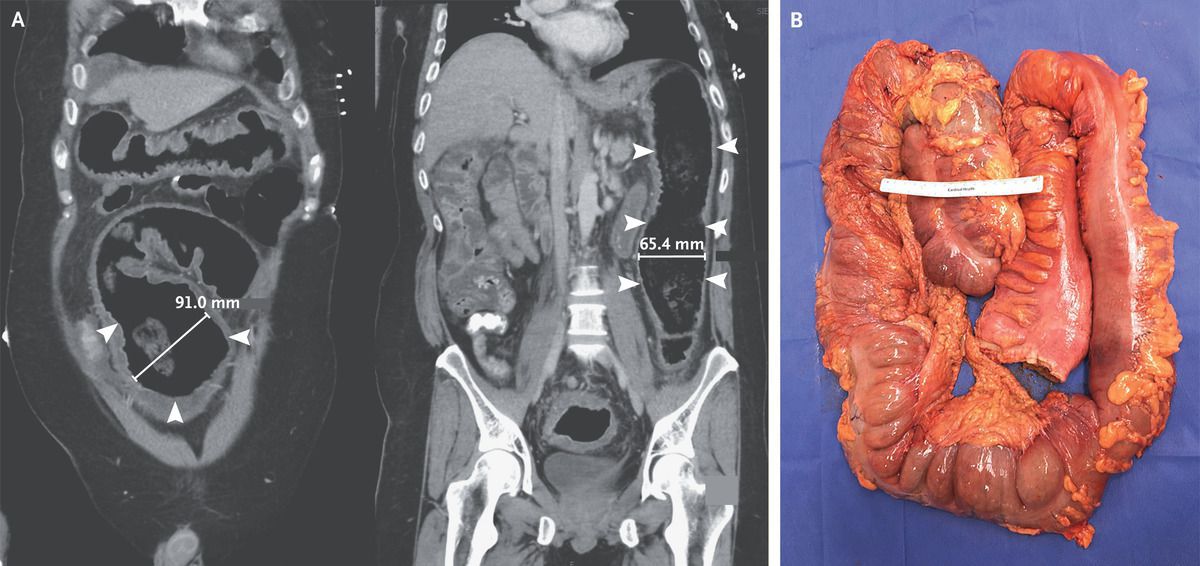

A 40-year-old man presented to the emergency department with vomiting and diarrhea. He had no known medical history and had not received antimicrobial therapy recently. His heart rate was 132 beats per minute, and other vital signs were normal. Examination was notable for confusion and for diffuse tenderness to palpation of the abdomen with tympany. Laboratory testing showed a white-cell count of 29,000 per cubic millimeter (reference range, 4000 to 10,800) and a positive nucleic acid amplification test for Clostridioides difficile. Computed tomography of the abdomen revealed pancolitis with distention of the sigmoid and descending colon (Panel A; arrowheads indicate the areas of distention, and two-dimensional measurements of colon width are shown). Despite 2 days of treatment with oral and rectal vancomycin and intravenous metronidazole, shock developed in the patient on hospital day 3. An urgently obtained radiograph of the abdomen showed worsening distention of the transverse colon near the hepatic flexure to 120 mm (abnormal width, >60 mm). Owing to concern for toxic megacolon due to fulminant C. difficile colitis, an emergency total colectomy with end ileostomy was performed. Gross pathological examination showed colonic dilatation with pseudomembranes (Panel B). Histopathological assessment showed pseudomembranous colitis, a finding consistent with C. difficile infection. The patient did well after surgery and was discharged 6 days after the procedure.